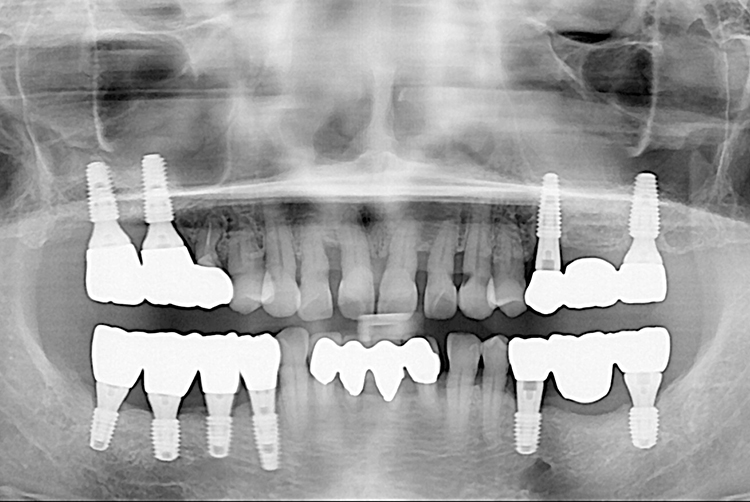

[임플란트] 임플란트

치료후 : 2021-06-09

세종치과는 많은 환자와 다양한 케이스를 바탕으로 항상 편안한 임플란트 수술을 제공하고자 노력하고,

오래동안 튼튼히 쓸 수 있는 임플란트 수술을 가장 큰 목표로 삼고 있습니다